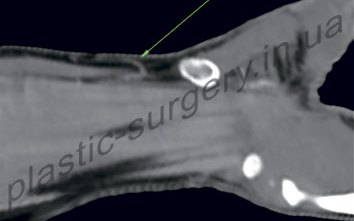

При подготовке к операции в клинике проводится компьютерная томография с ангиографией, что позволяет точно определить локализацию и состояние искомого перфоранта (Рис. 2).

Рис.2 Компьютерная томография с ангиграфией позволяет визуализировать локализацию и состояние тыльного перфоранта локтевой артерии (обозначен стрелкой) и восходящей кожной ветви; дистальнее визуализируется гороховидная кость, которая также используется как ориентир при дизайне лоскута.